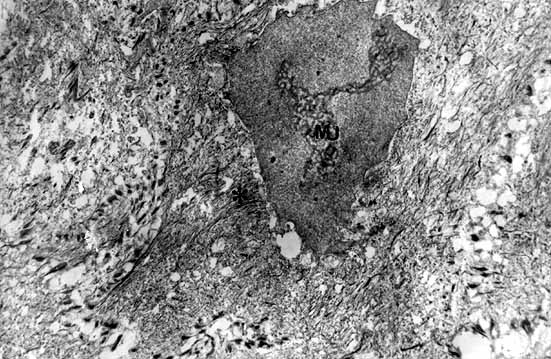

FIGURA Nº 5

FIGURA Nº5.- CELULAS PARABASALES CON INTENSA VACUOLIZACION ,PERDIDA DE TONOFILAMENTOS Y NUCLEOS INDENTADOS. AUMENTOS ORIGINALES 3500X